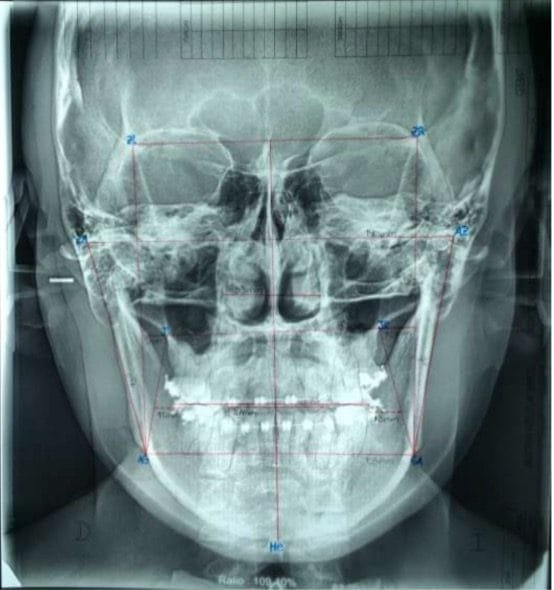

Radiografía: se ve la asimetría facial con canteamiento del plano oclusal así como mandibular y maxilar, Sobre la que se trazó la cefalometría inicial. (Fig. 5)

Fig. 5 Cefalometría frontal de inicio.